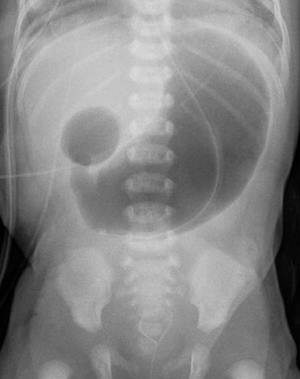

Double bubble (radiology)

In radiology, the double bubble sign is a feature of pediatric imaging seen on radiographs or prenatal ultrasound in which two air filled bubbles are seen in the abdomen, representing two discontiguous loops of bowel in a proximal, or 'high,' small bowel obstruction. The finding is typically pathologic, and implies either duodenal atresia, duodenal web, annular pancreas, and on occasion midgut volvulus, a distinction that requires close clinical correlation and, in most cases, surgical intervention.[1][2][3] Distal gas is more often seen with midgut volvulus, duodenal stenosis and duodenal web, though this not always present. In such cases, distinguishing the diagnoses depends on clinical presentation.[4] A fluoroscopic study known as an upper gastrointestinal series is often the next step in management in patients that are not critically ill, though if volvulus is suspected, emergent surgical intervention is mandated. If clinical findings are equivocal, caution with non water-soluble contrast is needed, as the usage of barium can impede surgical revision and lead to increased post operative complications. Non ionic water-soluble contrast should be used, as the hyperosmolar agents, if aspirated, can result in life-threatening pulmonary edema. When reflective of duodenal atresia, associations with Down's syndrome and VACTERL sequence abnormalities are often seen.[5]